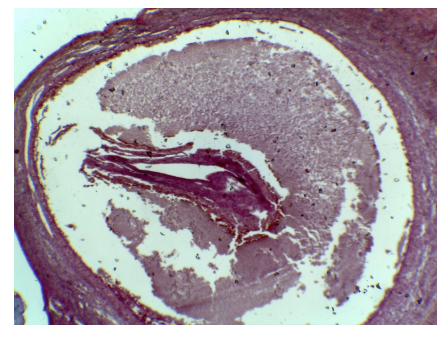

what is this

tertiary follicle

What is this

mature follicle

red

cumulus oophorus

orange

tertiary follicle

yellow

intermediate tertiary to mature follicle